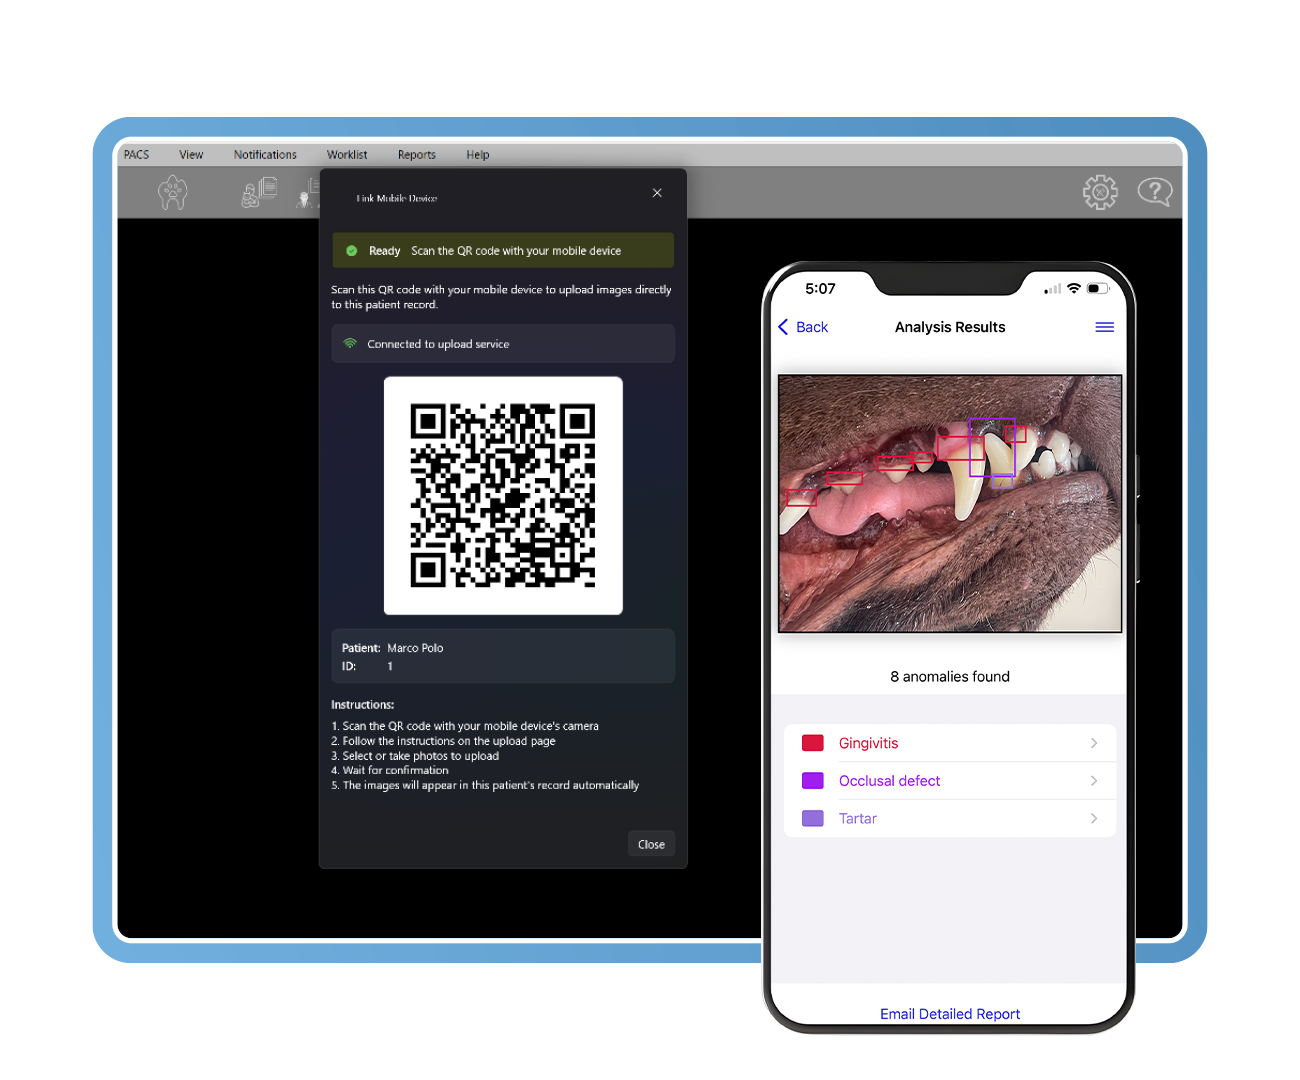

Imágenes conectadas con el cliente

Vincule de forma segura teléfonos y tabletas a los historiales individuales de los pacientes, permitiendo que el personal o los propietarios de las mascotas carguen imágenes directamente en el expediente clínico. Estas imágenes facilitan consultas más claras, mejoran la comprensión del cliente y aumentan de manera constante la aceptación de tratamientos dentales de aproximadamente un 10 % a más del 60 %.

Clarity identifica más de 70 patologías dentales y orales utilizando datos fotográficos y radiográficos. Entrenado con casos revisados por pares de odontólogos veterinarios certificados por el consejo, resalta anomalías en menos de 0,5 segundos, apoyando - sin sustituir - el diagnóstico clínico y acelerando una toma de decisiones segura y fundamentada.